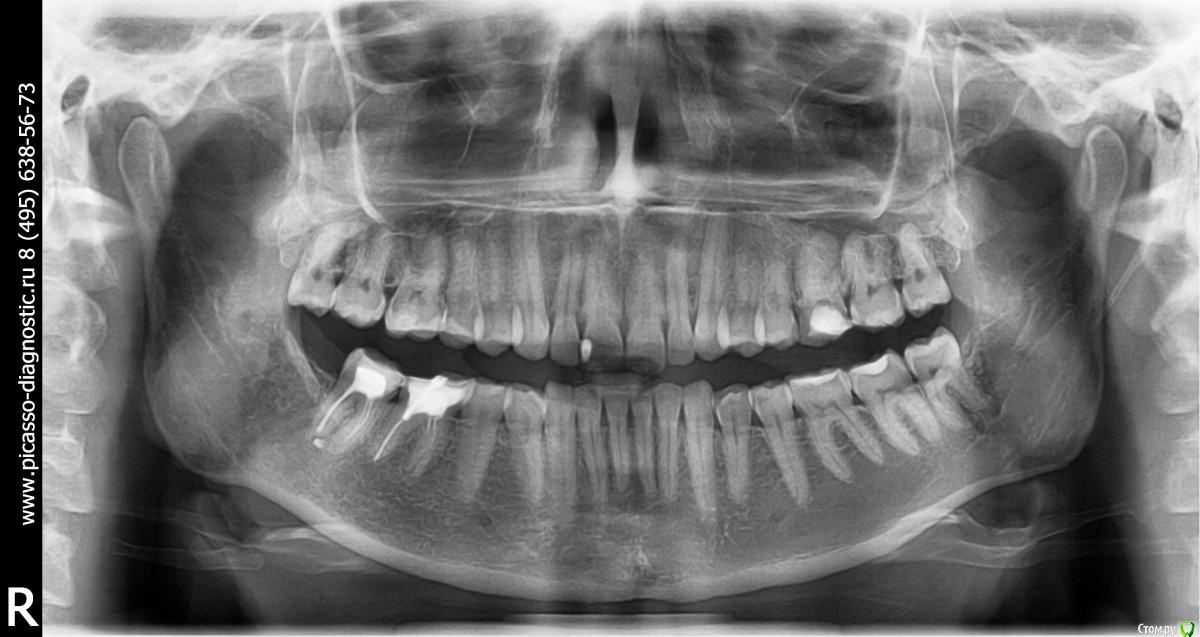

Olga82 Опубликовано 24 апреля, 2015 Поделиться Опубликовано 24 апреля, 2015 Прошу совета в нижеследующих проблемах:Зубы начала лечить с января 2105 года(Рентген-снимок именно до лечения прилагается), вылечила уже все зубы кроме одного(26-й или 16-й, не знаю, с какой стороны правильно вести отсчет).Проблема №1:Сделали верхние передние(замена пломбы+выравнивание режующей поверхности посредством пломб на обоих зубах+полировка(шлифовка).После шлифовки появились сначала белый точки, потом на зубе 1(фото прилагается) при чистке зубов прямо отошел тонкий кусочек как пленка полупрозначная зуба(зуб вообще был здоровый, только неровный рез), теперь там выемка как бы вглубь), на зубе 2 сейчас неровная как неотшлифованная поверхность (на фото, к сожалению, плохо видно, невозможно снять), на зубе 3 идет полоса на эмали-опять-таки как дефект шлифовки.Как это понимать? Топорная шлифовка или мои проблемы с зубами? дело в том, что я кормлю грудью уже 2 года, мой стоматолог сказал, что в зубах судя по всему мало кальция, поскольку после несильной заморозки один из них быстро побелел.Что мне предпринять? Дошлифовать недошлифованное?Или не трогать, а провести реминерализацию/глубокое фторирование/пропить курс витаминов и только потом их трогать? Какова судьба моих любимых передних зубов-печальная или смотреть оптимистично? Проблема №2:Дней пять как стали ныть нижние зубы(по фото обвела), их не лечили, они вроде как здоровые, небольшой коричневый налет присутствует с внутреннего края на одном, стоматолог его немного поскреб ....и смолчал...ничего не сказал...это камень, я правильно понимаю?Боль постоянная, тупообразная.Я полна мыслей об отстутствии кальция в моих зубах и слабости эмали купила пасту Лакалют сенситив, чищу ей второй день-пока нет результата, как болело, так и болит, полощу ротовую полость содой.Что это может быть?К стоматологу записана на 3 мая, не знаю, доживу ли до этого срока.Надо срочно бежать ?Спасибо всем за уделенное время моим проблемам. Ссылка на комментарий

faity Опубликовано 25 апреля, 2015 Поделиться Опубликовано 25 апреля, 2015 все что недоудолено- доудалить(1.8, 2.8, 3.8), все что недобрекетированно-добрекетировать, после ортодонтии еще и допротезировать(2.6, 4.6, 4.7) вопрос не по теме: почему кормите 2 года?О_о Ссылка на комментарий

Olga82 Опубликовано 25 апреля, 2015 Автор Поделиться Опубликовано 25 апреля, 2015 все что недоудолено- доудалить(1.8, 2.8, 3.8) Это чёй-то? У меня показания к удалению только одного зуба(я с номерами уже запуталась, он наверху). все что недобрекетированно-добрекетировать Это зачем это? Всё так плохо что ли? Ну не идеально ровно, согласна....но мне как-то всё-равно, особо не заметно ни мне, ни окружающим нестоматологам.Мой врач сказал, что прикус нормальный, без претензий на идеальность, но жить можно без ущерба здоровью зубов.Вы считаете, что в этом есть обязательная необходимость?В мои то года? еще и допротезировать(2.6, 4.6, 4.7) Остальное все уже сделано, запломбировано и запротезировано.Снимок январский....после чего раз в неделю как на работу уже ухожу..... вопрос не по теме: почему кормите 2 года?О_о Я не сумасшедший фанат долгого кормления, так сложилось в силу объективных причин согласованных с педиатором.Планирую завернуть через пару месяцев. Скажите мне, пожалуйста, отчего могут быть сколы эмали на зубах после полировки и белые точки? Ссылка на комментарий

faity Опубликовано 25 апреля, 2015 Поделиться Опубликовано 25 апреля, 2015 я написал офигительно длинный пост и случайно все удалил(((поэтому вкратце: отчего могут быть сколы эмали на зубах после полировки и белые точки? сколы из-за неправильного распределения нагрузки во время жевания, неправильное распределения нагрузки- из-за неправильного прикуса, пятна либо недополировали, либо после полировки покрыли адгезивом, чтобы "блястело сразу в кресле" Это чёй-то? У меня показания к удалению только одного зуба(я с номерами уже запуталась, он наверху). показания ортодонтические .Мой врач сказал, что прикус нормальный, без претензий на идеальность, но жить можно без ущерба здоровью зубов.Вы считаете, что в этом есть обязательная необходимость? Прикус патологический и если эстетика вас не напрягает, то артрит височно-нижнечелюстного сустава начнет рано или поздно давать о себе знать. Плюс читайте выше про ударные нагрузки и к чему это приводит. Ссылка на комментарий